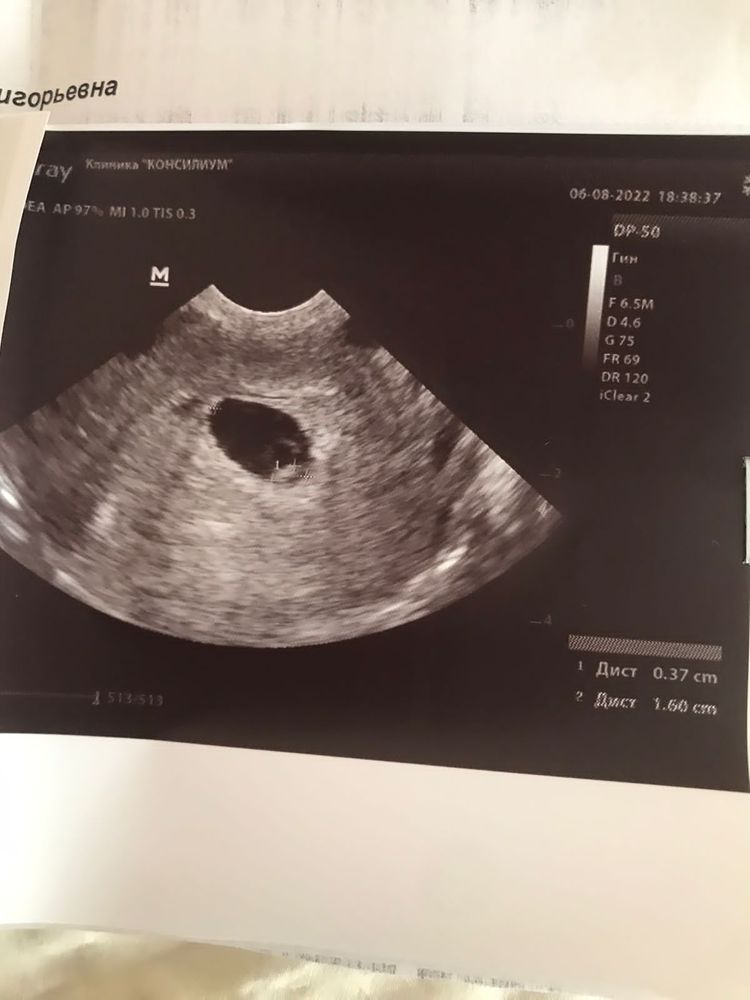

Замершая беременностьПоследние месячные 23.06.22

Поставили ЗБ,потом через 5 дней в другой больнице сердцебиение увидели.

19.08 была на УЗИ уже в ЖК опять вопрос в к сердцебиению то ли есть слабое,то ли совсем нет…

Врач говорит возможно поздняя овуляция…по КТР тоже вопрос сначала был 3.7 потом на другом аппарате 2 ( при этом хгч вырос почти в 2 раза) и через неделю 4 …

напротив сердцебиения стоит плюс, значит все хорошо! тьфу тьфу тьфу на вас